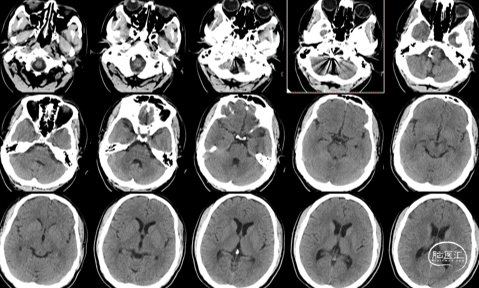

头颅CT:

蛛网膜下腔出血,以脑干前方密度较高,

并逆流入四脑室。

术后检查:次日CT

术后4天,肺部CT显示吸入性肺炎明显好转

术后14天,头颅CT示蛛网膜下腔出血完全吸收,头痛缓解,痊愈出院。

术后3个月门诊复查,恢复良好,无头痛及认知功能障碍,已恢复正常工作。头颅CT正常,无脑积水表现。MRA显示椎动脉血流通畅,无明显复发。